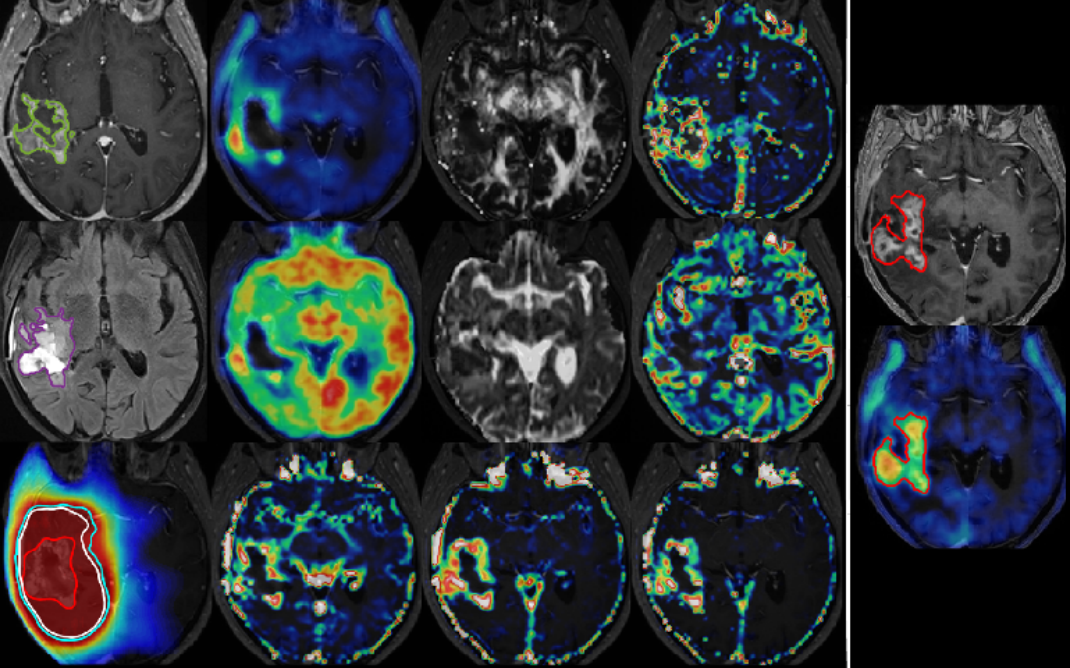

神经系统疾病的“侦察兵”

对阿尔茨海默病(老年痴呆)、帕金森病等神经退行性疾病的早期诊断,提供一站式评估。同时对脑肿瘤的良恶性判断、治疗后复发与放射性坏死的鉴别,为后续治疗提供可靠证据。

▲恶性胶质瘤高复发危险区评估图像